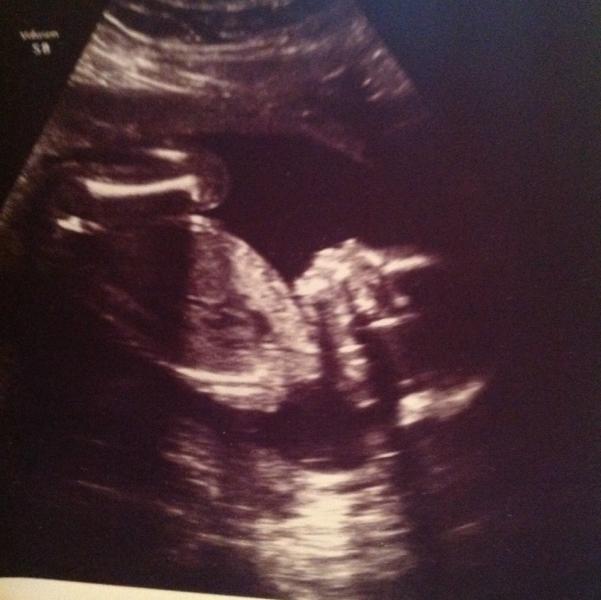

2-е УЗИ))) 💎💎💎ждем маленькую малышеньку))))) любимый с таким восторгом смотрел на экран, когда его кровиночка устроила танцы))) 💏💏💏конечно, ждал мальчика, теперь привыкает) а я с первых 2 полосочек знала, что будет девочка)!!! 🎊🎉🎊🎉🎊🎉🎊🎉💃💃💃💃💃моя принцесса)👑👑👑❤️💚💜💙💖